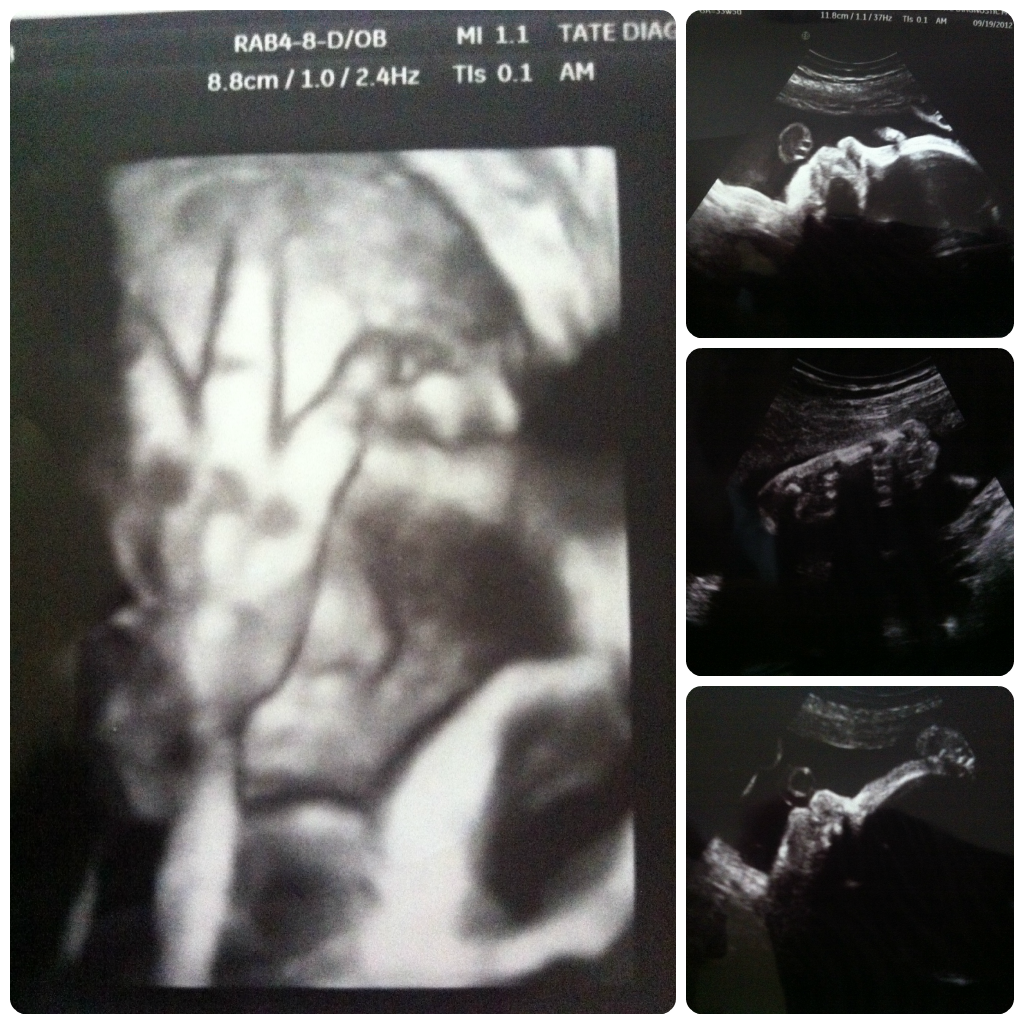

9.19.2012

I had a dr appt on Monday 9.17.12 and the dr measured me and like every other appt I was measuring small. Since I've measure consistantly small she ordered me an u/s to go make sure that Miss Kendall was growing right. The nurse made me an appt for Wed morning bright and early at 8am. I had to wake up the girls and drop them off at Grandma's and drive about 20 mins to my appt. I haven't had to be up that early in a long time!! So I got to my appt and they took me back right away. The guy u/s tech was super nice and funny. He explained everything he was doing as he was doing it and said that everything was measuring right on and little miss is perfect. He said she has long legs, which she had right up by her face the whole time. He switched it over to 3D a few times and it was so cute to see her. Not sure who she looks like cause it was hard to see her with her hand in her front of her face or her leg. But she is a cutie. So everything checked out perfect with her.

At 33 weeks 5 days Kendall is weighing in at 4lbs 14oz

At 35 weeks Keira was weighing in at 5lbs 10oz

At birth Keira weighed 7lbs 1oz